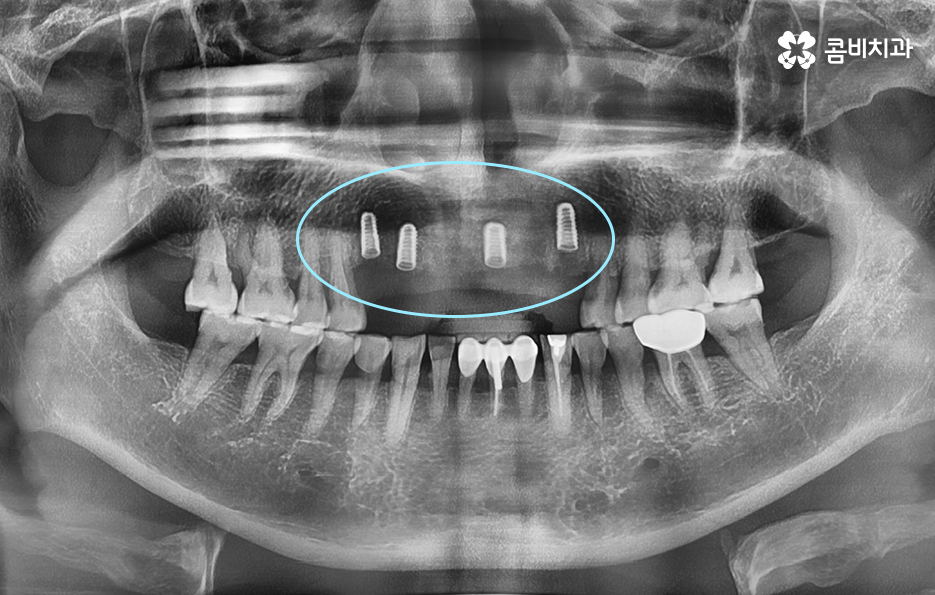

임플란트 치료는 되도록 치아를 상실한 개수와 1:1로 비례하여 식립하는 것을 권장하고 있는데 그 이유는 치아의 저작력에 있어서 우리의 모든 치아를 각각의 역할과 기능이 있고 압력에 대한 분산 효과도 있는데요

따라서 앞니임플란트를 해야하는 경우에는 치아를 잃게 될 경우 곧 바로 치료를 하는 것이 중요하며 임플란트의 수명과 심미성을 위해서도 치아를 잃은 개수만큼 치료하는 것을 권장하고 있는데요.

잇몸 상태와 전신 건강이 양호한 경우에는 원데이임플란트를 통해 앞니임플란트 치료를 많이 진행하지만 오늘 케이스처럼 이미 치아를 발치한 후 시간이 지난 경우나 치주염으로 인해 잇몸 뼈가 녹고 염증이 심한 경우에는 빠른 치료보다는 잇몸을 충분히 회복하여 건강하고 안전한 결과에 더 초점을 두고 있는데요.

각 개인에 따라 치료 계획은 1:1 맞춤형으로 진행되고 있으며 임플란트는 치료를 잘 받는 것과 함께 사후 관리를 잘하여 오랫동안 문제없이 수명을 잘 유지하는 것에 더욱 초점을 둬야하기 때문에 치료 시점 뿐 아니라 치과 선택에 있어서도 잘 따져보실 필요가 있어요